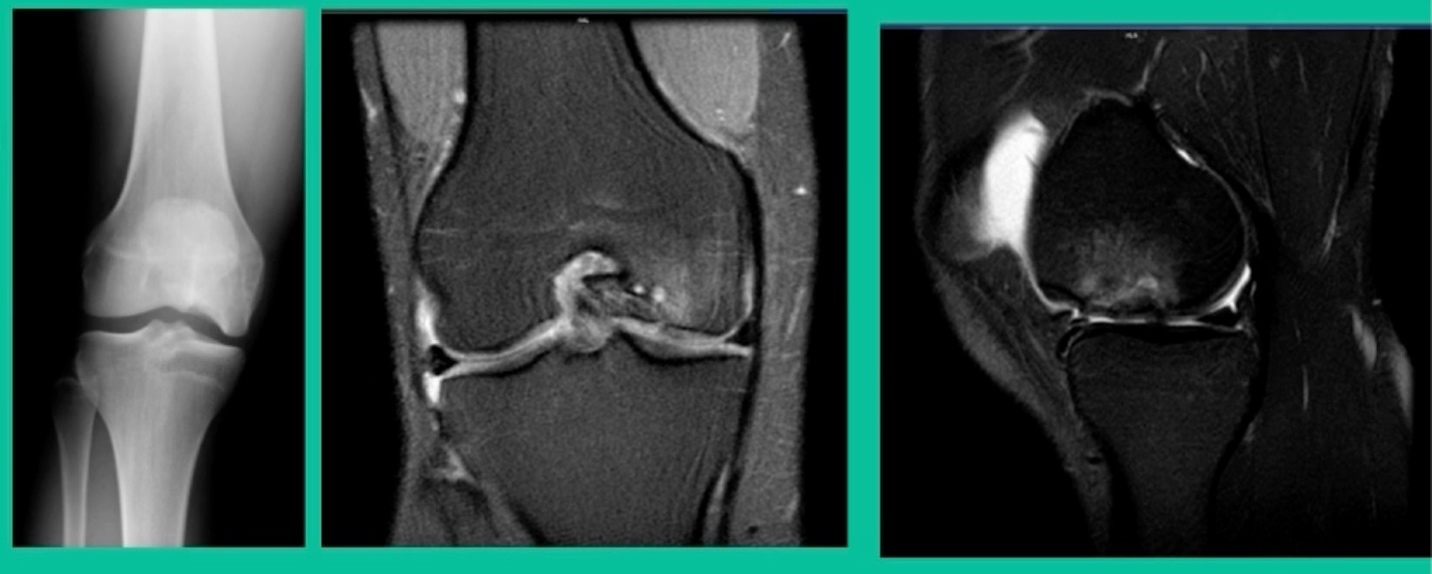

This is an 11-year-old. Left knee lateral knee pain. Effusions, the same type of classic findings (Figure 3)

You look at this one, you say, “what are you going to see when you get in there?” This is one when you get in there, you say, I’m not even sure I’m in the right knee because you almost don’t see it. That happens in patients who were painful, but they don’t look macroscopically unstable. Pediatric orthopedic surgeons tend to drill these. These are the ones that I see as failures. I think when you’re talking about something that’s mechanically unstable, it’s hard to understand why drilling would actually make it work without fixation. Even if it’s microscopically unstable.

The challenge is this. This series of patients were populated by early decisions to treat when patients don’t have symptoms. That’s a problem in my mind. Post-Op, they protect their weight-bearing. That’s actually treatment. These are often smaller lesions of the medial femoral condyle. They do really well. That being said, it’s an option. It’s not my option. My option for someone who’s macroscopically unstable is we use biocomposite screws (Figure 4).

These biocomposite screws will hang around for upwards of a year. So, they’re not innocuous, and you’ve got to bury their heads. But we drill it, we tap it, and we stabilize it, and then we drill from the side in an effort to promote further biology. This is analogous to just arthroscopic fixation, but I don’t go back, and I don’t remove the screws. Then I’ll typically take a K-wire from the side after I place these screws. I keep them non-weight-bearing for eight weeks. I don’t remove it. I wait four months before they go back to high-impact activities like this patient did here.

What are the outcomes? Very, very favorable. We had 87% survivorship using a biocomposite screw. Would I use it for a macroscopically unstable one? I wouldn’t. I would tell you that the biomechanics are not nearly as good, and it is not innocuous. If you leave the head proud, this will scratch the tibia and cause a railroad track there. You must bury them, but don’t take them out.